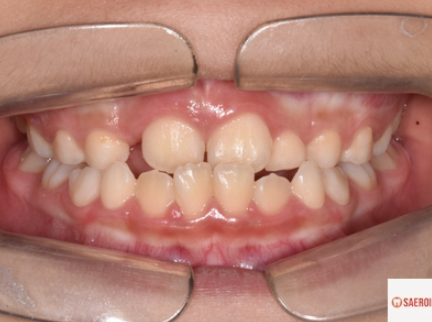

왼쪽이 교정 전 오른쪽이 교정 후입니다.

정상적인 앞니 덮임을 보여주고 있습니다.

가운데 앞니 양옆으로

치아가 나올 공간이 부족했었으나

상악 악궁 확장을 동시에 시행하여

양측 두 번째 앞니가 잘 내려오고 있습니다.

이는 아래의 파노라마 사진에서도 확인할 수 있습니다.

미소 시 보다 심미적인

위아래 앞니 관계를 보입니다